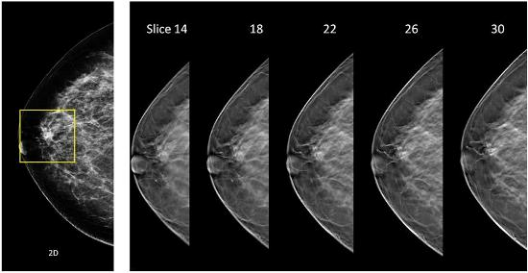

En este procedimiento diagnóstico el tubo de rayos que realiza la mamografía es móvil y obtiene múltiples imágenes y desde un mayor número de ángulos para luego combinarlos en una imagen tridimensional.

Esta tecnología avanzada ayuda a los radiólogos a detectar tumores más pequeños y a diferenciarlos de otras estructuras en la mama, por lo que es una herramienta muy útil para diagnosticar el cáncer de mama de una forma más precisa y temprana. Esto ha mejorado la prueba aumentando las tasas de detección del cáncer de mama un 35% y la sensibilidad y especificidad de la mamografía, reduciendo significativamente indicaciones de biopsias innecesarias.

En 2023 incorporamos un nuevo mamógrafo 3D con tomosíntesis de alta resolución (70 micras) e imagen sintetizada, que minimiza la dosis de radiación a nuestras pacientes.